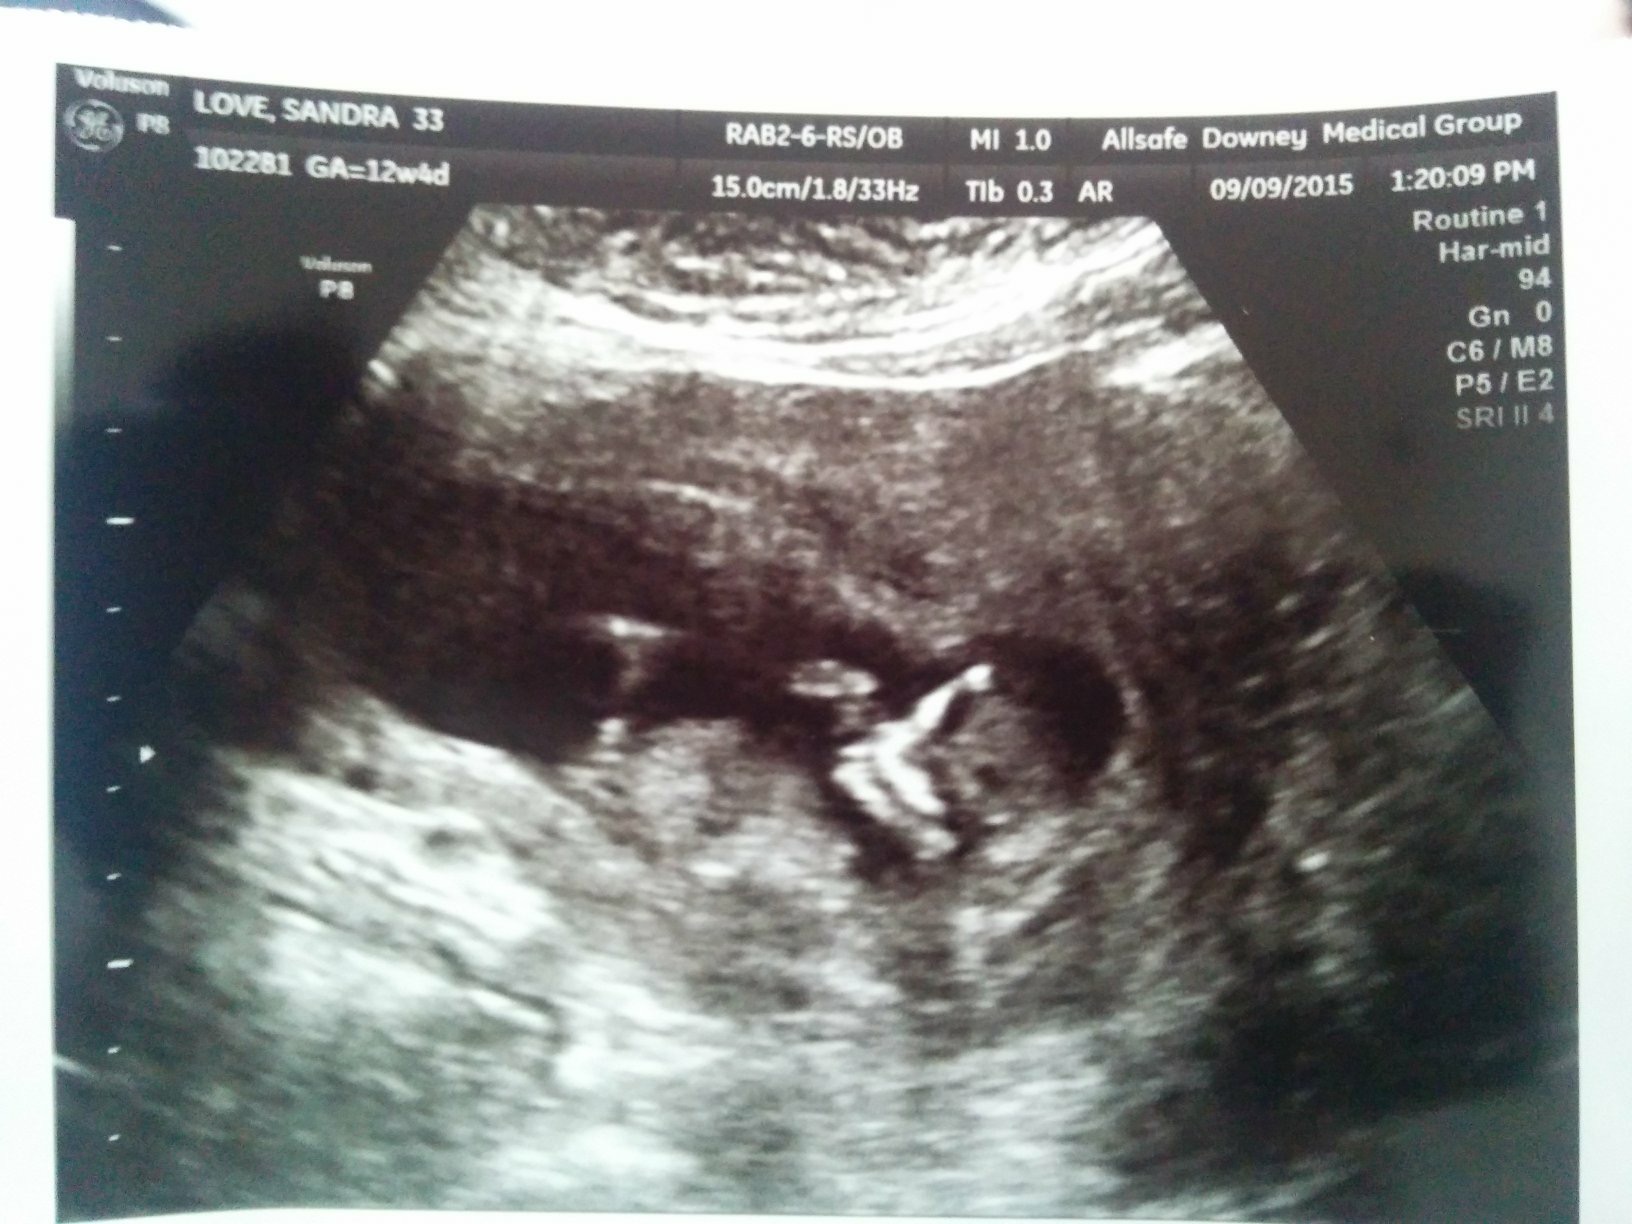

Here is another pic taken the same day. I'm not sure the angle is correct in this one though. Attachment 28637

I guess boy from the second pic.